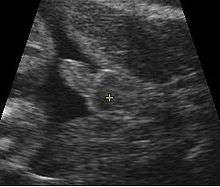

Artificially colored, showing gestational sac, yolk sac and embryo (measuring 3 mm as the distance between the + signs).